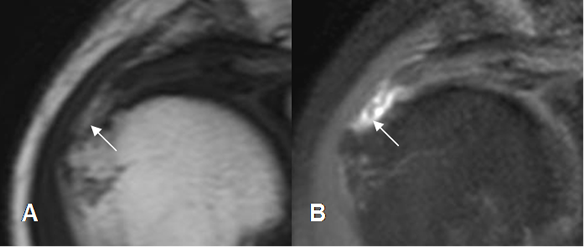

Fig 123. Ruptura del supraespinoso.

A: RM coronal en T2y B: RM coronal en STIR. Ruptura completa del tendón, con espacio ocupado por líquido.